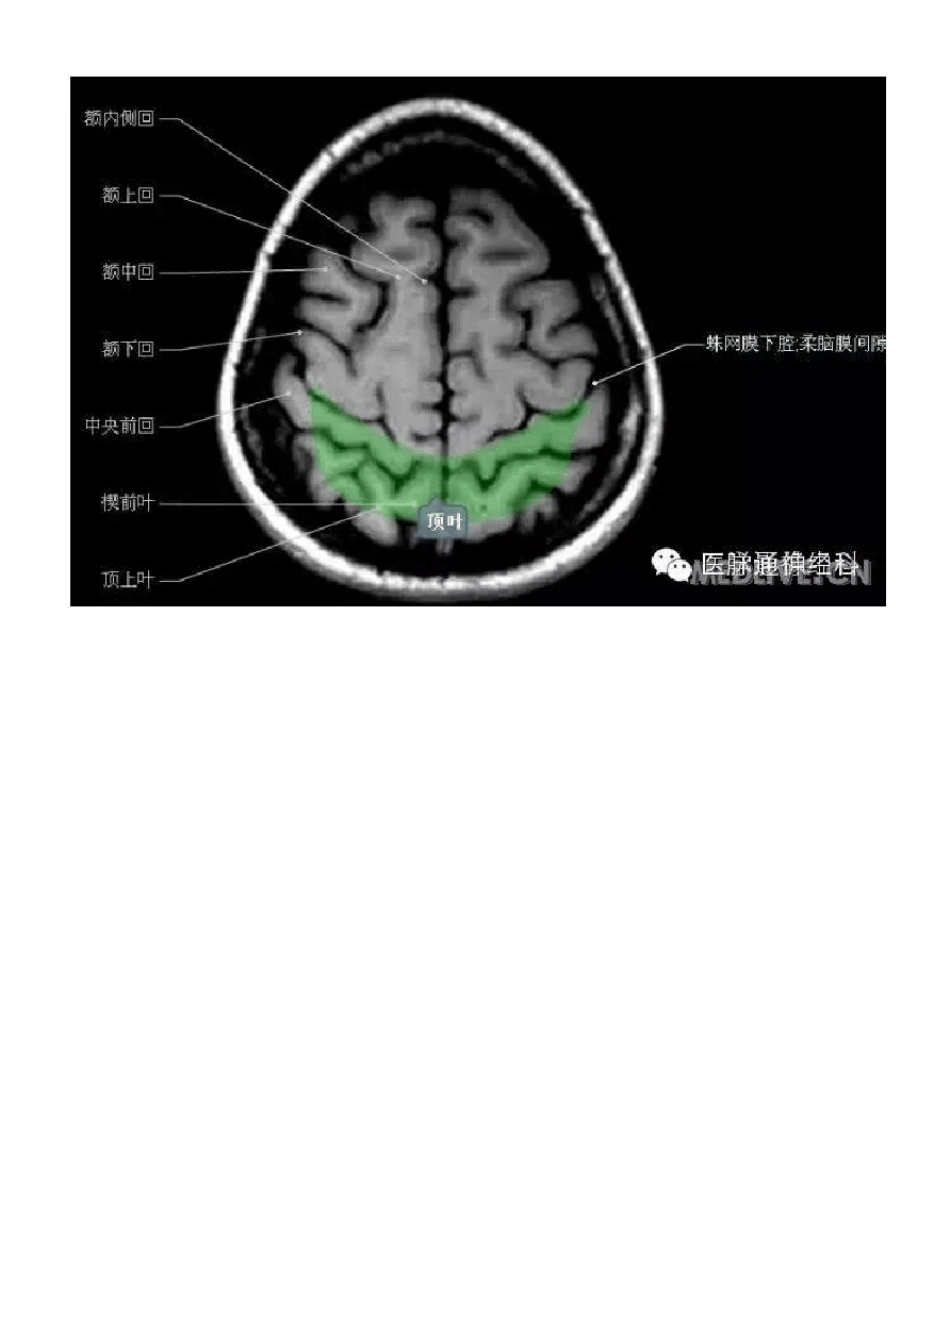

正常颅脑MRI 图示

正常颅脑磁共振图示